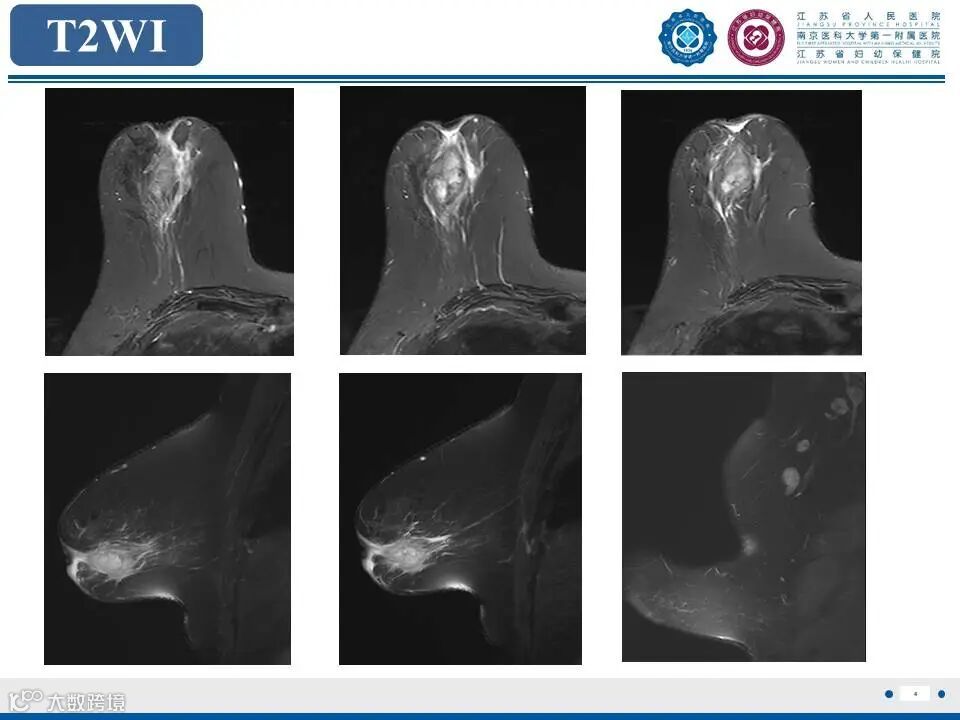

非哺乳期乳腺炎